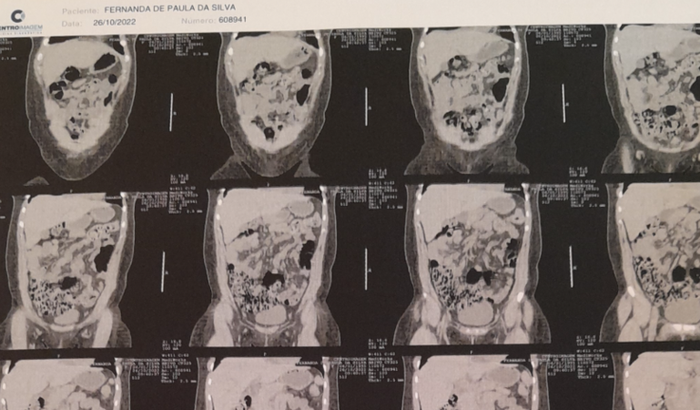

Olá,me chamo Fernanda! Gostaria de pedir sua ajuda pra fazer uma cirurgia de cálculo renal com urgência. Meu rim já está comprometido,o cálculo está obstruindo a saída da urina,correndo o risco de perder o rim. Sinto muita dor e infelizmente não dá pra esperar na fila do SUS.Preciso arrecadar o valor de 7.500,00. Qualquer valor será bem vindo. Desde já agradeço sua colaboração!